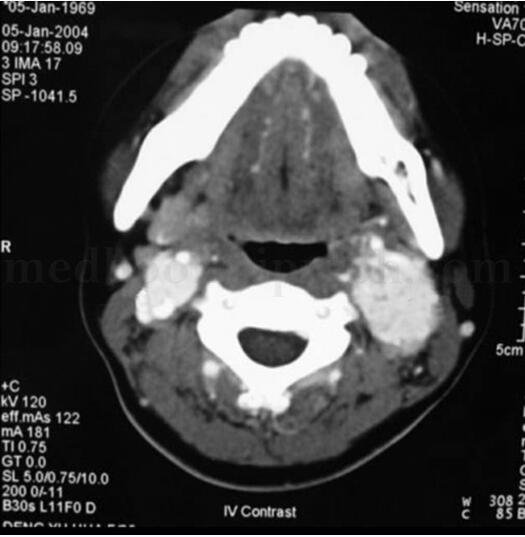

腹部CT未见异常;UCG提示左室肥厚,舒张功能降低;MIBG(-);奥曲肽显像示双侧颈动脉及纵隔右前方异常放射性浓聚区,考虑多发异位嗜铬细胞瘤;心脏增强CT显示心脏后方肿瘤(图31-4);颈部增强CT见左、右侧颈动脉分叉处直径5cm、3cm肿瘤(图31-5);冠脉造影回旋支近段发出心房支向瘤体供血,造影中有两次血压突然增高,最高达200/125mmHg,经硝普钠等治疗后可控制正常。

图31-5 颈部CT示双侧颈动脉分叉处肿瘤